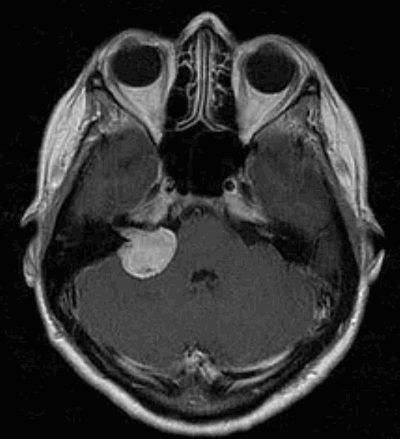

Наиболее информативным методом выявления вестибулярных шванном является МРТ головного мозга с контрастным усилением в режиме Т1 и Т2. Это исследование позволяет определить размеры опухоли, наличие перитуморозного отека, наличие признаков окклюзионной гидроцефалии, которая может быть следствием сдавления опухолью IV желудочка. Кроме этого МРТ позволяет провести дифференциальную диагностику с другими опухолями схожей локализации (чаще с менингиомой задней грани пирамиды височной кости). Еще одним стандартом диагностики является КТ в костном режиме. Независимо от снижения слуха стандартом является проведение аппаратной аудиографии.

Сканирование головы: если другие тесты показывают, что у пациента может быть вестибулярная шваннома, для подтверждения диагноза используется магнитно-резонансная томография (МРТ). МРТ использует магнитные поля и радиоволны, а не рентгеновские лучи для создания подробных изображений мозга. Томография показывает «срезы» мозга, которые можно объединить для создания трехмерного изображения опухоли. Часто пациенту вводят контрастный краситель. Опухоль впитывает больше красителя, чем нормальная ткань мозга, и будет четко видна на сканировании. МРТ обычно показывает опухоль во внутреннем слуховом проходе.